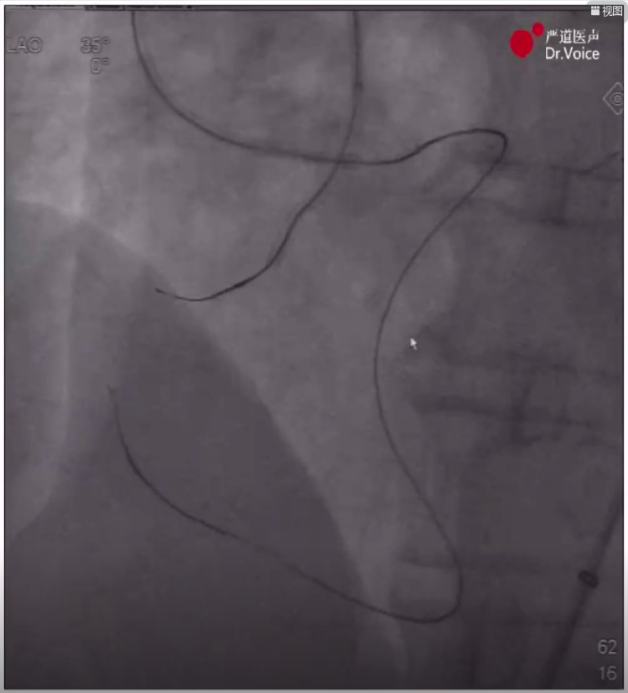

7、重新送入导管后,调整正向和逆向导丝重叠,通过AGT技术将逆向导丝送入正向指引导管,正向球囊锚定逆向导丝后,跟进逆向corsair150微导管至正向指引导管,正向runthrough导丝穿逆向微导管后完成轨道建立。

逆向导丝进入正向导管内